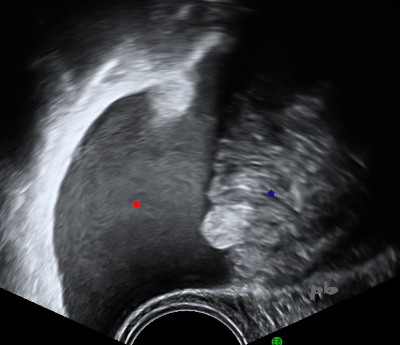

2-GEU associée à une grossesse bichoriale biamniotique

- Epanchement échogène dans le Douglas (★).

- Anses digestives flottant dans l’épanchement (★).